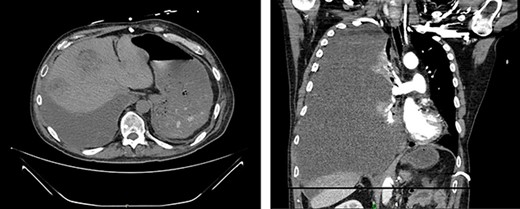

Appearance of effusion in the left retroperitoneal space in transverse (left) and coronal (right) planes on CT; it can be seen encroaching on the spleen; subsequent cytology ruled of malignant effusion.

Two weeks post-resection, the patient was recovering as expected. At 4 weeks post-resection, radiation oncology recommended 7 weeks of intensity-modulated radiation therapy to both the surgical site and at-risk nodes identified on CT. Six weeks post-resection, the patient presented to the ED with nausea and vomiting. Abdominal CT revealed a retroperitoneal effusion at the surgical site (Fig. 3). At this admission, the patient also tested positive for COVID-19, delaying drain placement and his radiation treatments for 2 weeks.